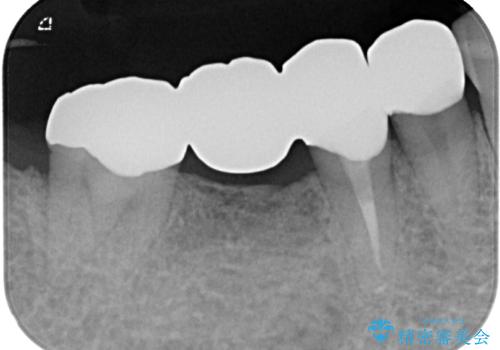

詰め物が割れた フルジルコニアクラウン

- 左下の4番目のセラミックの詰め物(セラミックインレー)が欠けたとのことで来院された患者様です。以前にセラミックの詰め物の治療を行い、噛み合わせが強く割れてしまっていました。今回はセラミックの詰め物のやり替えだとまた欠けてしまう可能性があるのでフルジルコニアクラウンでの治療を行うことにしました。拡大鏡視野下でセラミックの詰め物、虫歯を除去しフルジルコニアクラウンに適した形に整えました。

歯と歯茎の間に圧排糸と呼ばれる糸を入れてシリコーン印象を行いました。

見た目、機能面ともに満足していただけました。

噛み合わせが強い方なので今後はセラミックが割れないようにナイトガードを使っていただきながら、定期的にクリーニングで通ってもらう予定です。